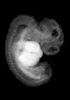

Carnegie Stage 17 (41 post-ovulatory days)

Most embryos at stage 17 are approximately 41 postovulatory days old and measure 11-14 mm in length. Distinguishing criteria for this stage include distinct digital rays in the hand plate, a rounded digital plate in the foot, a complete complement of hillocks on the mandibular and hyoid arches, distinct nasofrontal grooves, and a slight indication of a lumbar curvature.

This specimen does not represent normal development. The caudal nueral tube has failed to close properly.